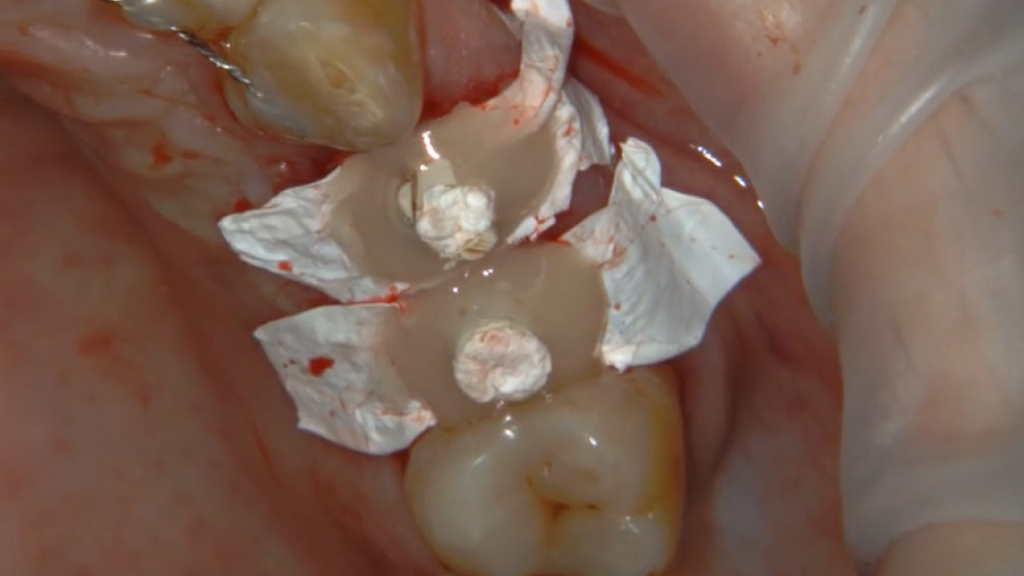

Описание клинического случая:

• Атравматичное удаление зуба 2.4, 2.5

• Одномоментная дентальная имплантация IMPRO

• Использование фибриновой мембраны Clot-PRF

• Установка временного абатмента IMPRO

• Изготовление индивидуального формирователя десны

Клинический случай Узденовой Зульфы Альбертовны